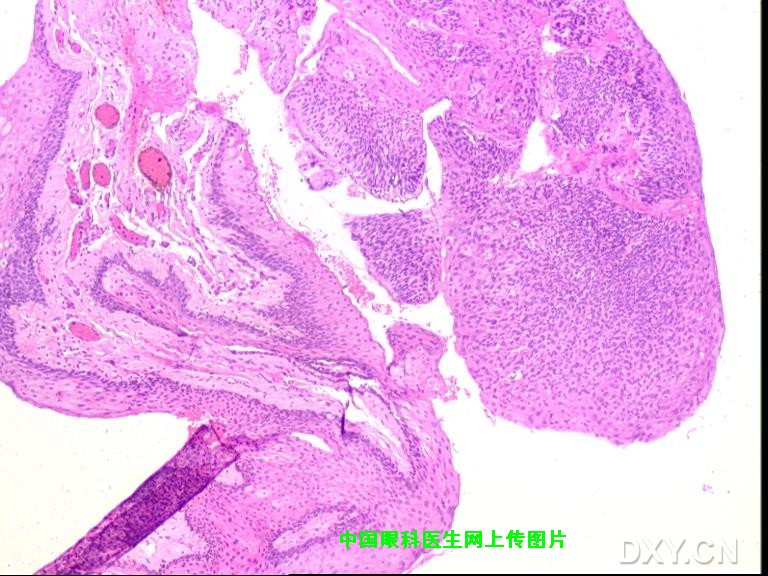

以下为病人术后2周照片。 病理报告:鳞状上皮乳头样增生伴轻度不典型增生。

非常感谢您所提供的图片,从形态上看,的确与我所报道的病例极为相像,随之而来的是诊断上的困惑,我们诊断为Bowen病(角膜上皮内上皮癌)的主要依据如下: 1.睑裂区角膜缘病变,灰白色半透明隆起,发展缓慢且症状轻微; 2.手术当中非常容易剥离,说明病变没有突破基底膜; 3.当然最有发言权的应该是病理所见(金标准);我曾将病理图片发到丁香园病理讨论区,但回应者不多,看来还是得请咱们眼科特别是病理方面的同行来给大家解释一下该病例的病理图片。 另外如果可能也请您将您所报道病例的术后情况以及病理所见提供给大家。

感谢提供的文献,看来我们的病理取材后的处理手法有待提高,切除的组织发生了卷曲。 |